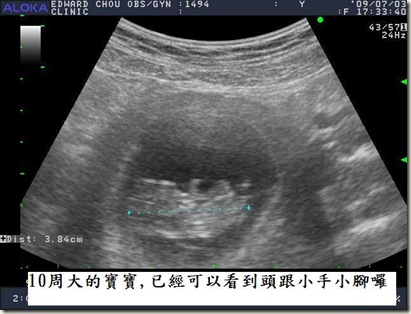

10周大的baby           從三月開始,跟老公努力拼老二,連續槓龜了兩個月後,老公說,不如去法國度假,回來再努力。五月初,就在法簽拿到,機票飯店都付款之後,發現自己懷孕了!哈哈!呼呼……雖然有一點點意外,但是還是很開心啦。